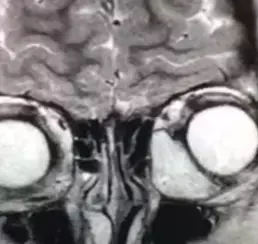

Рисунок 6. МРТ глазных орбит с контрастированием. На фоне проводимой терапии состояние без динамики, в связи с чем проведено дообследование: КТ орбит и МРТ орбит с контрастом. КТ показало образование левой орбиты, активно накапливающее контрастное вещество. МРТ орбит с контрастом — образование левой орбиты 2,6×1,5×2,9 см, активно накапливающее парамагнетик (см. рис. 6).

— На МРТ мы видим образование, которое находится под верхней стенкой глазницы, тесно примыкает к глазному яблоку и мышцам (см. рис. 10). Проводим трансконъюнктивальную орбитотомию и выделяем образование, тесно связанное с верхней косой мышцей (см. рис. 11). К сожалению, ее при выделении образования приходится пересечь. Иммуногистохимическое исследование подтверждает эмбриональную рабдомиосаркому, — рассказывает офтальмохирург. — Пациент продолжил лечение у онкологов. На данный момент он в ремиссии уже 3 года. Мы прооперировали его по поводу вертикального непостоянного косоглазия, которое развилось вследствие того, что мы резицировали часть верхней косой мышцы.